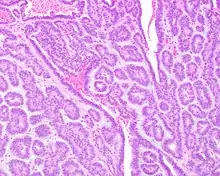

Tumors are usually small because they come to clinical attention early on in development, with an average size of about 1.6 cm.[1] There is a very characteristic appearance to the tumor when reviewed histologically.

There is a canalicular pattern with cords and ribbons showing connection points between opposing columnar cells within spaces that is called a "string of pearls" appearance.

There are often small luminal squamous balls or morules. There is a very well-developed supporting tissue that is a loose, fibrillar stroma, rich in hyaluronic acid and chondroitin sulphate.[1] In a few cases small calcifications or microliths may be present. Although seldom necessary, a pathologist can do immunohistochemistry studies to confirm the diagnosis, with the cells strongly reactive with pancytokeratin, S100 protein and SOX10, with a delicate GFAP reaction around the periphery.[5][1][6][7] Even though it is a benign tumor, it must be separated from a basal cell adenoma, pleomorphic adenoma, adenoid cystic carcinoma, and polymorphous adenocarcinoma.